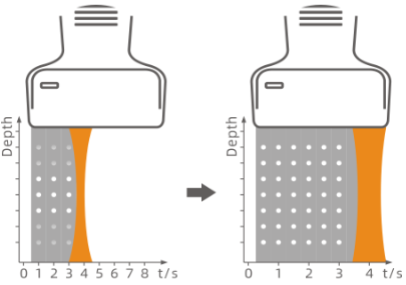

Pixel Echo Zone (PEZ)

During wide band imaging processing, the system automatically collects echo information by larger processing zone to enhance acquisition efficiency and computing speed. Increased image frame rate facilitates a better and faster diagnostic experience.

Target Focus

The image focus in near and far field requires different signal intensity. This upgraded technology provides automatic compensation in signal transmission to further improves focus accuracy and image uniformity in the entire image area.